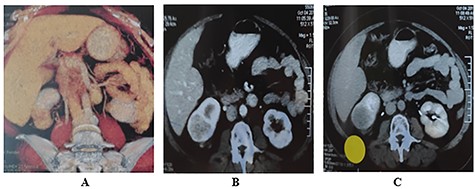

She was scheduled to take 30 sessions of radiotherapy and then to be on hormonal therapy in the form of Tamoxifen 20 mg/day for 5 years. During the last post-operative follow-up—3 months later—the patient complains of right hypochondrial pain; furthermore, the patient was scheduled for a multi-slice Triphasic Pelvi-abdominal CT which demonstrated the presence of a highly vascular renal mass with enhancement in the arterial phase and fading out in the later phases of examination suggestive for malignancy with patent inferior vena cava (IVC) and renal vein. There was no peri-renal or abdominal lymphadenopathy (Fig. 4).

Triphasic multi-slice pelvi-abdominal CT scan showing exophytic mass at the lower pole of Rt Kidney; (A) Colored 2D CT reconstruction; (B) Enhancement of tumor in the arterial phase; (C) Fading out of the contrast in the venous phase.